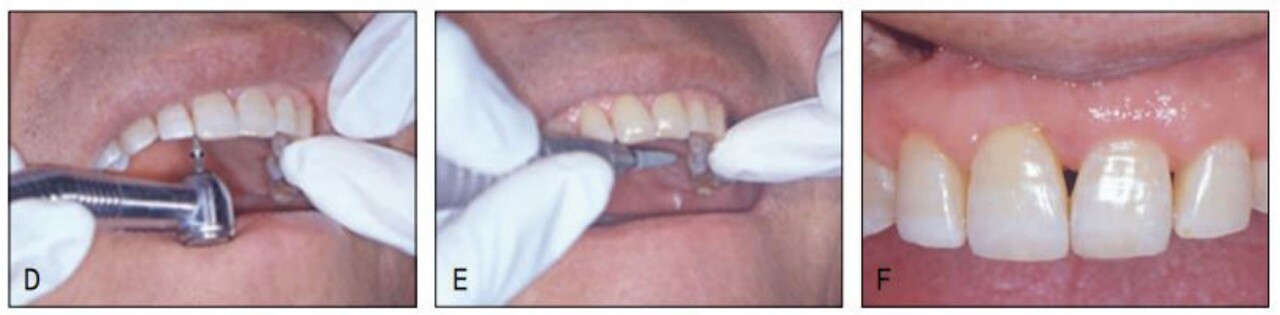

그러나 전치부 과개교합으로 상악설측면에서의 장치 부착이 불가하여 환자에게 투명교정장치를 설명하였고 이 역시 심미적 장치이어 환자가 수락하고 투명교정장치로 간단하게 공간클로져 교정을 시행 하였다. 가철식 장치이어서 다소의 경사이동이 발생하였고 치주질 환으로 우측의 중절치가 더 정출하여 비심미적인 절단연이었으나 스트리핑 그리고 re-shaping 등을 이용하여 심미적인 절단연을 만들어주었다. 교정을 주저하였던 환자는 설측및 투명장치 등 심미적 장치로 인해 교정치료 내내 크게 만족해 하였다(그림 23-7~10).